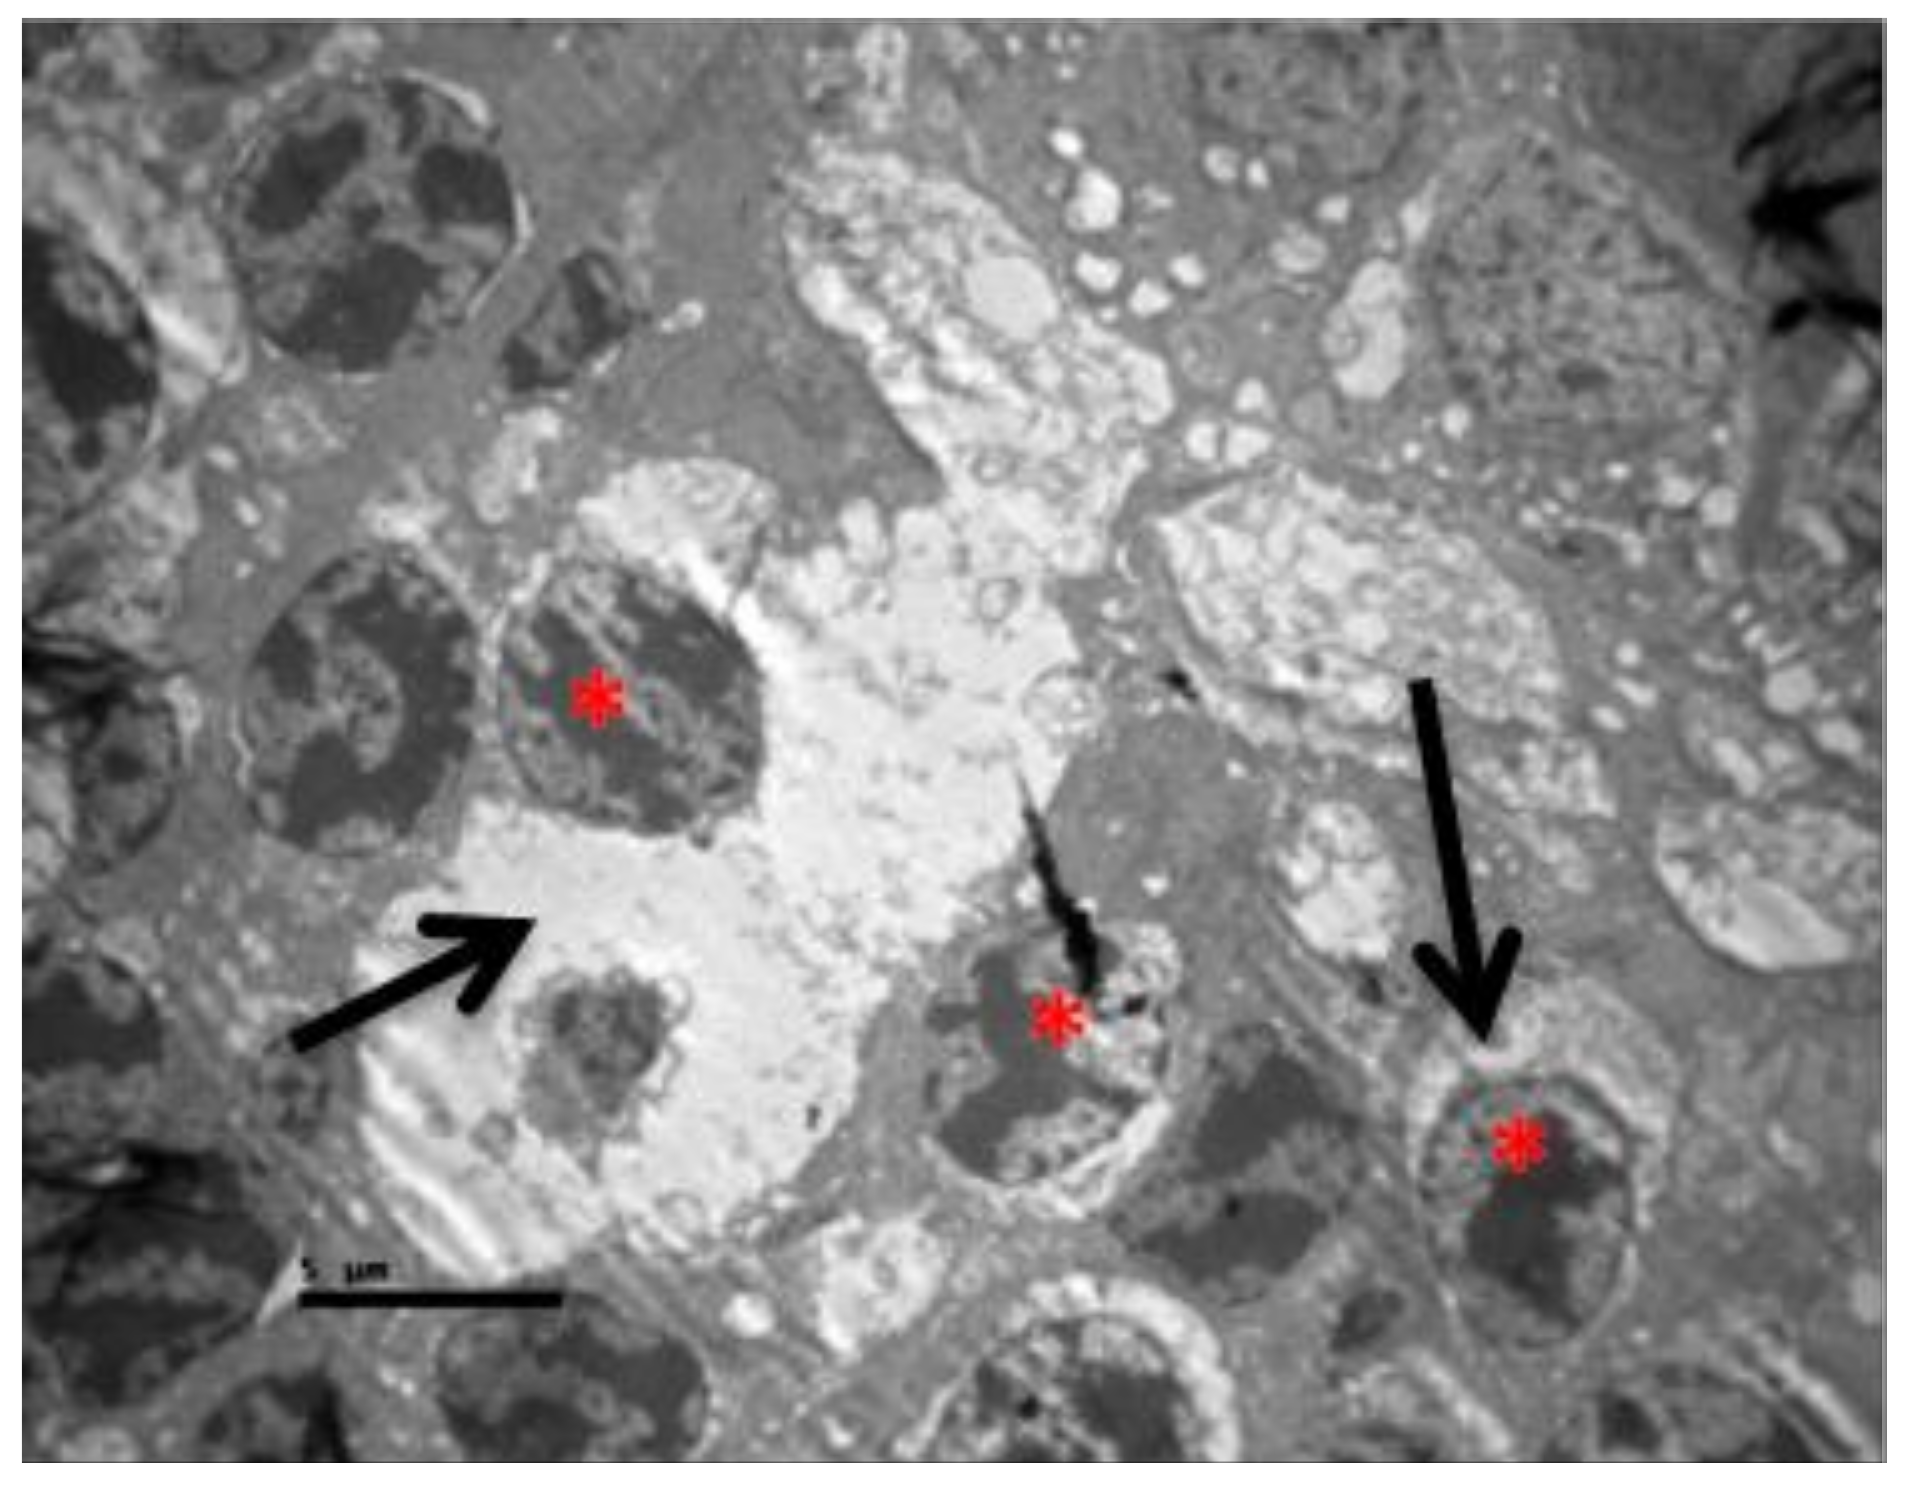

2.1. Group C

2.2. Group V

2.3. Group M